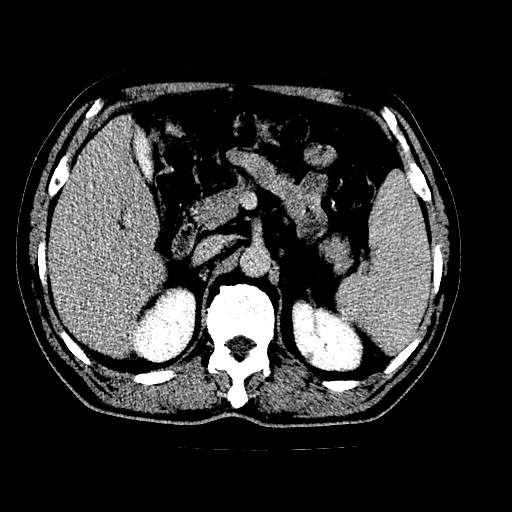

男,66岁,上腹部不适、黄染一周。彩超示:肝左叶占位,肝内胆管扩张,胆总管扩张,胆总管占位?

肝左叶不规则软组织肿块影,边缘不规整邻近肝实质受累分界不清;肝内胆管(左叶)明显扩张成“软藤状”,诊断:肝左叶胆管细胞癌。

肝左叶占位性病变,并胆管扩张,符合胆管细胞癌ct表现,门脉左支受累,左肾囊肿。窗宽太窄了,其他的看不清

左叶胆管细胞癌累及胆总管,门脉左支受侵,慢性胆囊炎胆结石,左肾小囊肿